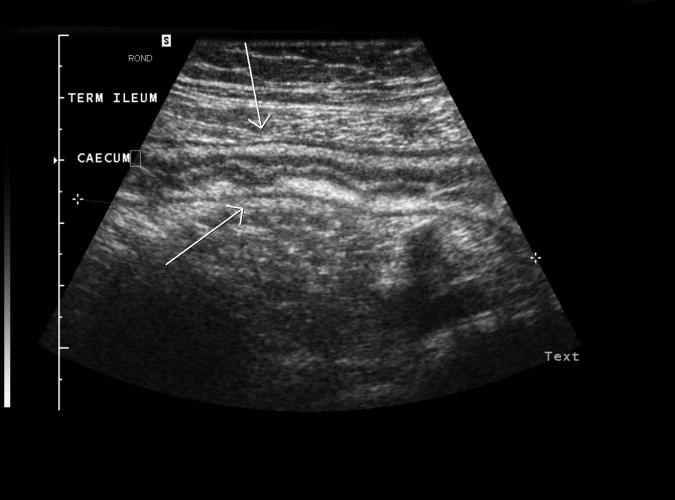

Patologi.

Frågeställning GB stenar. Ultraljud visas gallstenar men

dessutom en gastom, väggförtjockad term ileum och föreslår

Crohns sjukdom. Enterografi bekräftar fyndet.